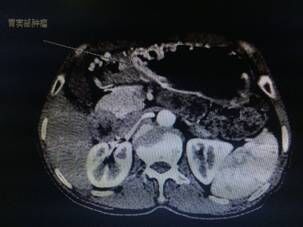

我院胃腸外科今年3月收治一名男性患者,以反復腹痛7月入院,CT提示胃竇部及乙狀結腸占位性病變(分別見圖1、2),行內(nèi)窺鏡活檢分別考慮胃腺癌以及乙狀結腸絨毛狀腺瘤,不排除惡變傾向。為改善患者生存率,減少創(chuàng)傷,手術團隊決定充分發(fā)揮腹腔鏡技術優(yōu)勢,采用腹腔鏡下一期同時切除胃、結腸病變,由于患者乙狀結腸病變惡性診斷不明確,根據(jù)腫瘤根治的原則,先處理乙狀結腸。手術當中依據(jù)冰凍切片,在腹腔鏡下首先完成乙狀結腸癌根治,后行腹腔鏡下遠端胃癌根治術。一次微創(chuàng)手術,切除兩個腫瘤,免除了患者傳統(tǒng)剖腹手術及二次手術的創(chuàng)傷,縮短了住院時間,術后恢復快,降低了患者住院費用。

圖片1                               圖片2